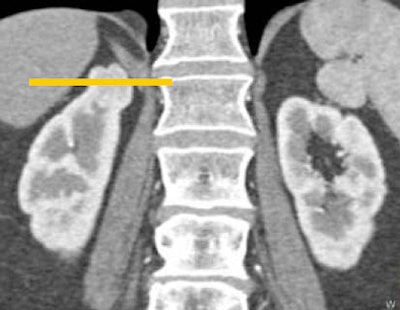

The image display format is also important, Fishman said. Findings at the poles of the kidneys tend to be easy to miss on axial images and more readily seen in coronal images, which are especially useful in renal imaging, he said.

| Multiplanar views are important in renal imaging, especially coronal displays (top), which can reveal findings not seen in axial views of the same region (bottom). |